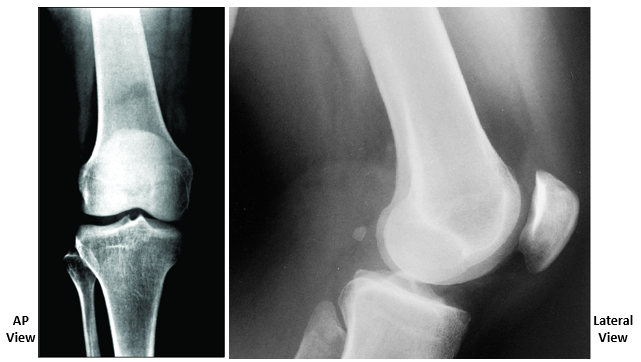

• Bones of Knee Joint

•Modified hinge joint

•3 separate articulations:

–Femoropatellar

–Femorotibial (x2)

Fibula does NOT articulate at the knee joint

• Bones of the Knee Joint

• Articular Surfaces